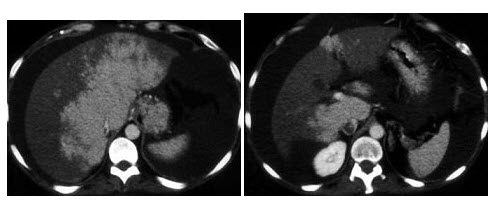

8、单项选择题

根据所提供的图像,该病例的最可能的诊断为()

A.肝癌

B.布-加氏综合征

C.脂肪瘤

D.肝硬化

E.以上都不是

点击查看答案

本题答案:微信扫下方二维码即可打包下载完整带答案解析版《★放射医学(医学高级)》或《放射医学(医学高级):CT》题库